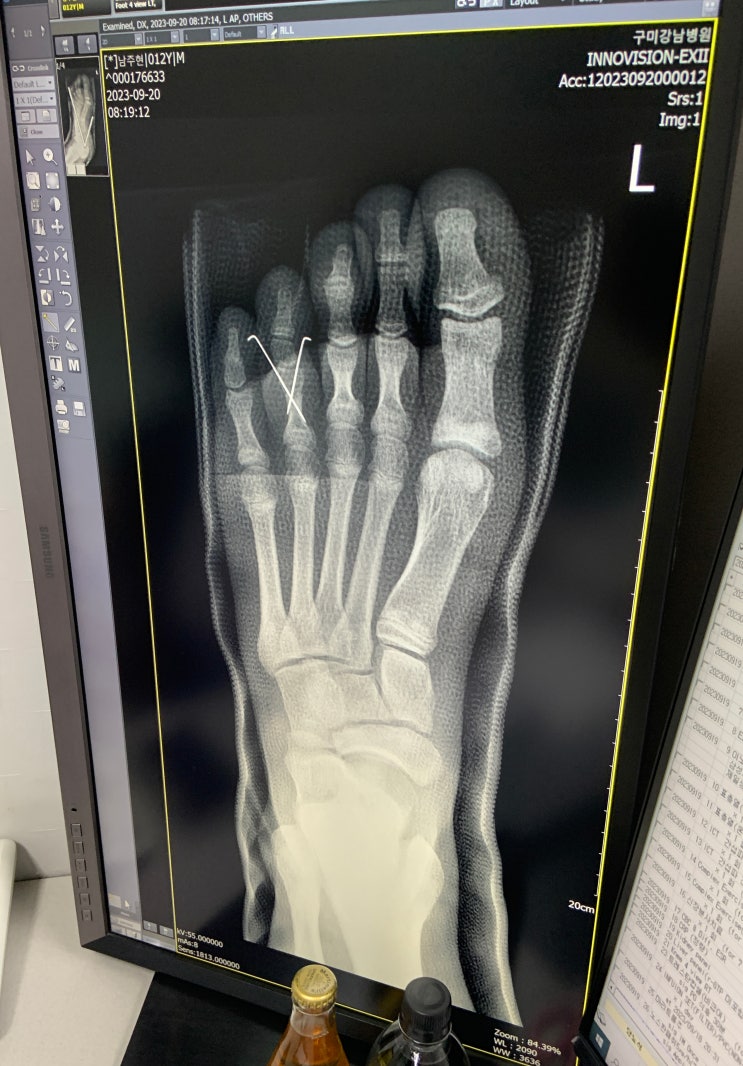

손가락 골절 반깁스, 발가락 골절 핀박는 수술 후기 남겨봐요.

#손가락골절 #손가락골절증상 #손가락골절반깁스 #손가락골절병원 #손가락골절붓기 #손가락골절보험 #발가...